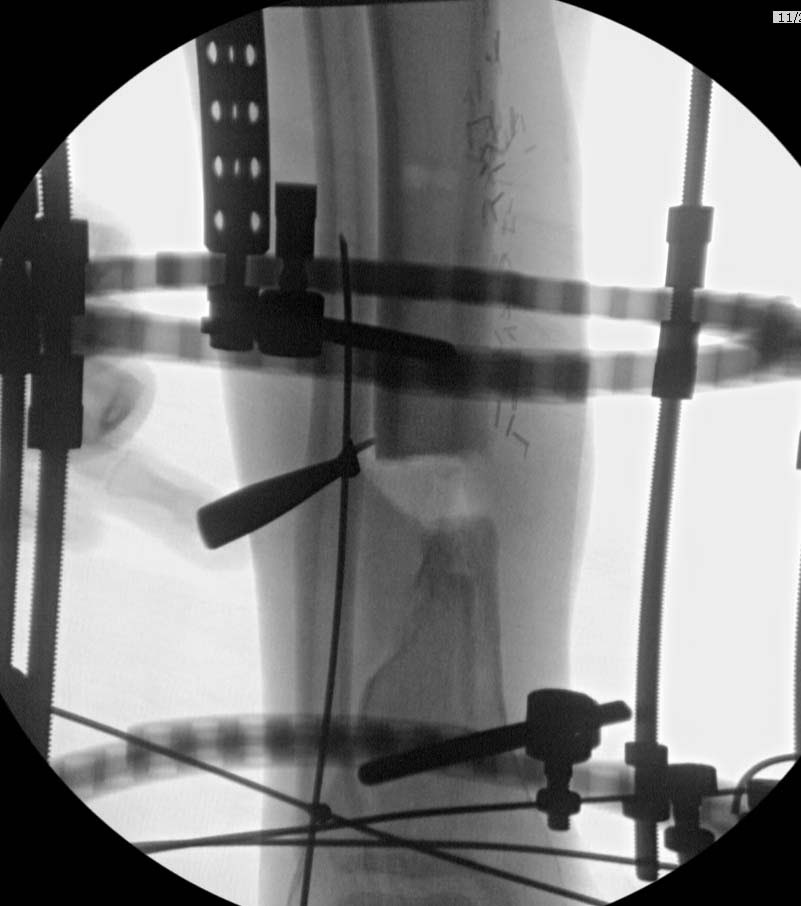

Данный случай не огнестрельная рана, а результат мотоциклетной аварии.

Независимо от повреждения при таких обширных дефектах мягких и костной

тканей применяется схожая тактика. Как видно, после нескольких I&D для

создания “pseudo membrane” применили цилиндрический блок из цемента.

Дефект мягких тканей закрыли свободным Anterior Thigh Graft. Из малого

доступа цилиндр удален небольшими кусочками, а пространство заполнили

бусами для освобождения пространства. По мере приближения регенерата

освободили пространство удалением бус через небольшой разрез. Этап

созревание регенерата можно было ускорить усилением интрамедуллярным

гвоздем, но решили закончить методом Илизарова.